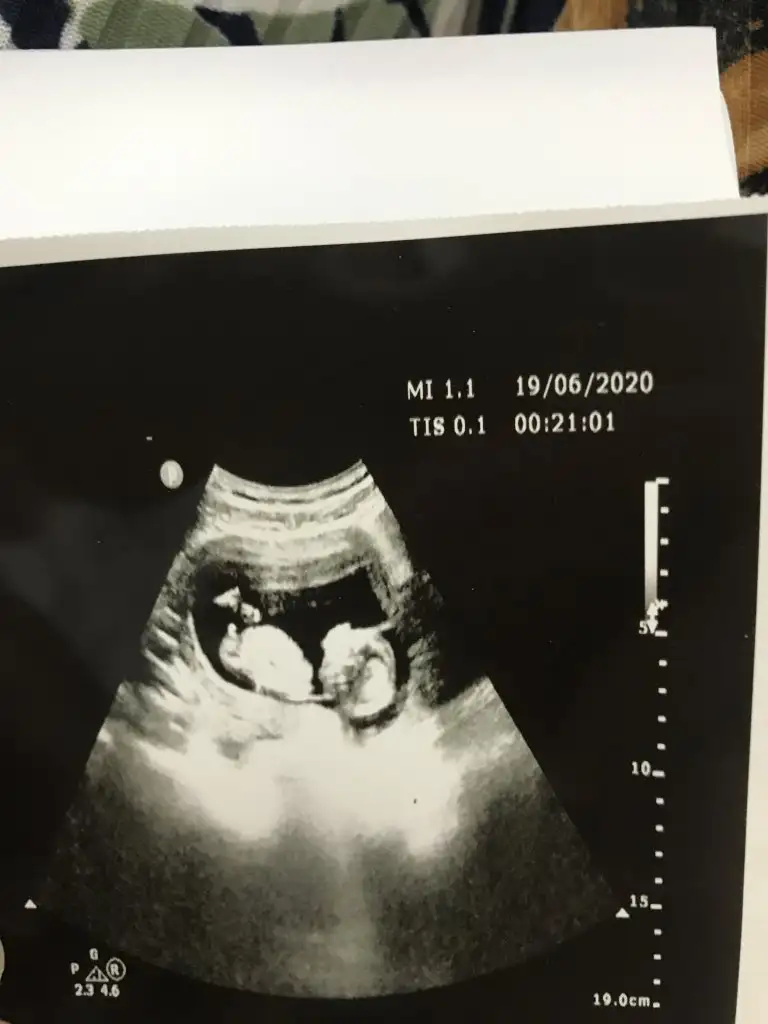

Bunlar net değilBi de bu resimler var.

Kaç haftalık usg sanki erkek gibi eminde olmadım 11 12 13 haft usgler olmalı tekrar usg paylaşınMerhabalar tahmininizi çok merak ediyorum :)

Üçlü taramada büyük ihtimalle kız olduğu söylendiNet degil usg tek tek çekermisiniz usgler yada başka usg olursa paylaşın 12-13 haftalarda olabilir şimdilik eminde değilim kız gibi gibi emin değilim tekrar usg paylaşın